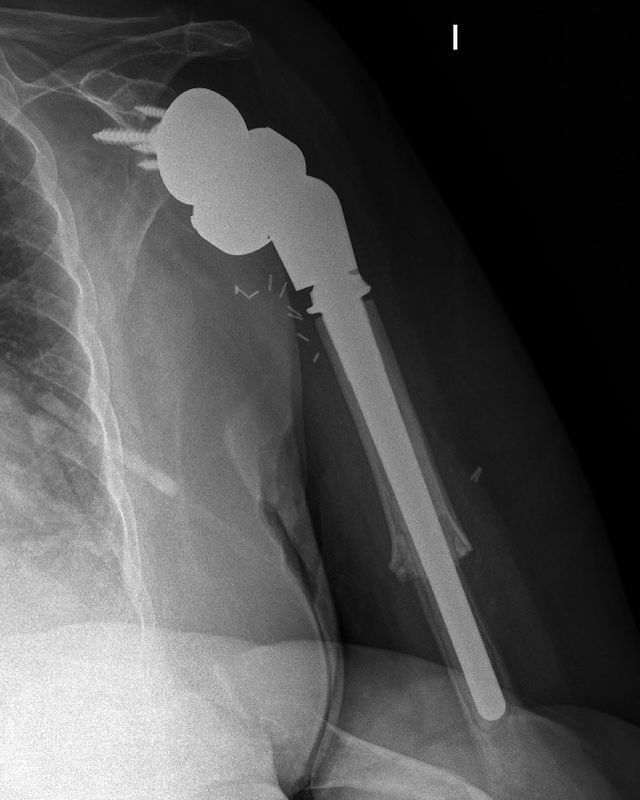

Condrosarcoma en húmero

Hoy me gustaría compartir el caso de una mujer de 72 años con un condrosarcoma G3 de humero izquierdo (imágenes 1,2),  a quien hace 1 año se le realizó una resección (imagen 3) y reconstrucción con la megaprótesis invertida Comprehensive SRS cementada de Zimmer Biomet. (imagen 4) Radiografía de control (5). A los 6 meses presenta un aflojamiento aséptico (imagen 6). Retiramos el componente humeral (imagen 7) y reconstruimos con un ALOINJERTO TELESCOPICO PRESSFIT (imagen 8) y un nuevo componente humeral mas corto (imagen 9) Radiografías de la reconstrucción AloProtésica (imagen 10)

Para poder ayudar a los pacientes con sarcomas debemos tener múltiples opciones reconstructivas, ya sea para el procedimiento inicial, como para las complicaciones que puedan surgir